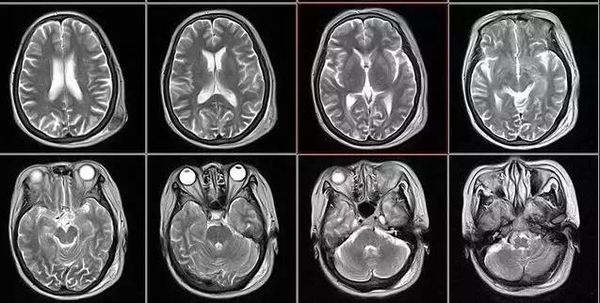

核磁共振

摇一摇再看

核磁共振机使用较强大的磁场,使人体中所有水分子磁场的磁力线方向一致,这时磁共振机的磁场突然消失,身体中水分子的磁力线方向,突然恢复到原来随意排列的状态。简单说,就相当于用手摇一摇,让水分子振动起来,再平静下来,感受一下里面的振动。所以,核磁共振也被戏说为是摇摇看的检查。